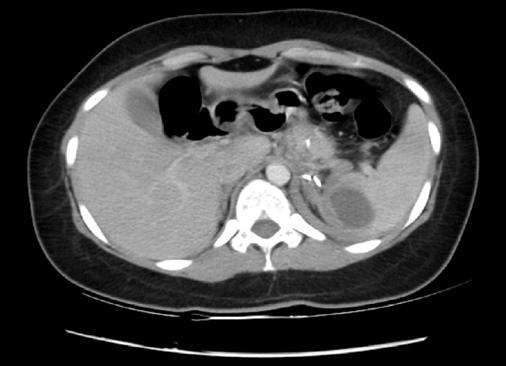

Se realiza tomografía computada (TC) de abdomen (doble contraste) con los hallazgos de infarto esplénico del polo superior (15% aproximadamente), mínimo derrame pleural izquierdo, y tubo gástrico indemne, sin evidencia de fugas ni colecciones intra-abdominales (Figuras 1-2).

Figura 1. Infarto esplénico en el polo superior. Tubo gástrico indemne